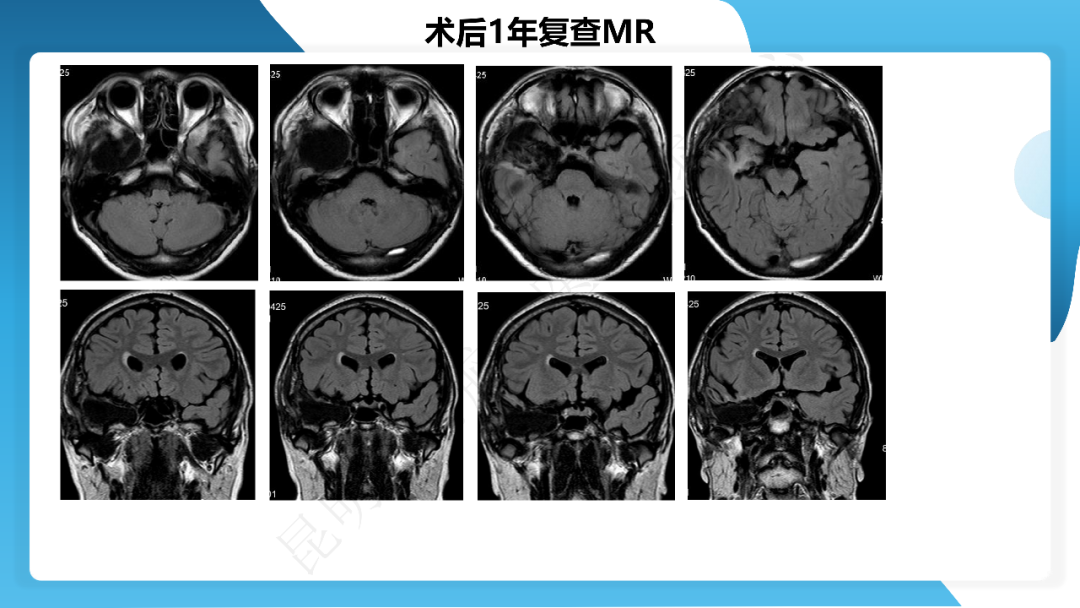

《「痫停」信步》癫痫治疗病例荟萃第三十六期---右侧颞前叶及内侧结构切除手术治疗局灶性癫痫一列